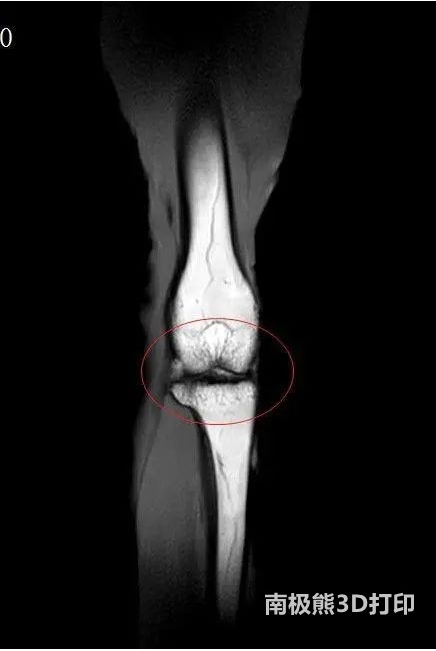

運用此技術修復的兔子膝關節軟骨已恢復如初

關節軟骨在肢體活動中起重要作用,隨著年齡的增大,關節纖維彈性會減弱,關節液減少使軟骨變得干燥,因此人到一定年齡,就容易膝蓋痛、走路難,關節軟骨的老化和損失已成為降低老年人生活質量的一大“殺手”。關節軟骨分為軟骨層,過渡層和軟骨下骨層三層,每一層的韌度和硬度都不相同。傳統的臨床手段如關節鏡清理術、注射透明質酸或膠原蛋白都無法模擬人類軟骨的復雜結構,不同硬度的修復材料放在一起也容易產生滑移和脫落,療效很不理想。如何實現軟骨缺損組織的一體化修復?科研人員想到了生物3D打印技術。